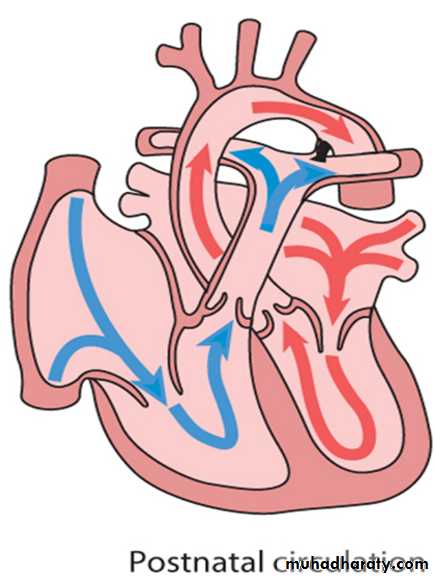

Circulatory changes at birth

In the fetus, the left atrial pressure is low, as relatively little blood returns from the lungs.The pressure in the right atrium is higher than in the left, as it receives all the systemic venous return including blood from the placenta.

The ductus arteriosus shifts the blood from the pulmonary artery to the aorta.

The flap valve of the foramen ovale is held open, blood flows across the atrial septum into the left atrium and then into the left ventricle, which in turn pumps it to the upper body.

With the first breaths, resistance to pulmonary blood flow falls and the volume of blood flowing through the lungs increases sixfold. This results in a rise in the left atrial pressure. Meanwhile, the volume of blood returning to the right atrium falls as the placenta is excluded from the circulation. The change in the pressure difference causes the flap valve of the foramen ovale to be closed. The ductus arteriosus will normally close within the first few hours or days.